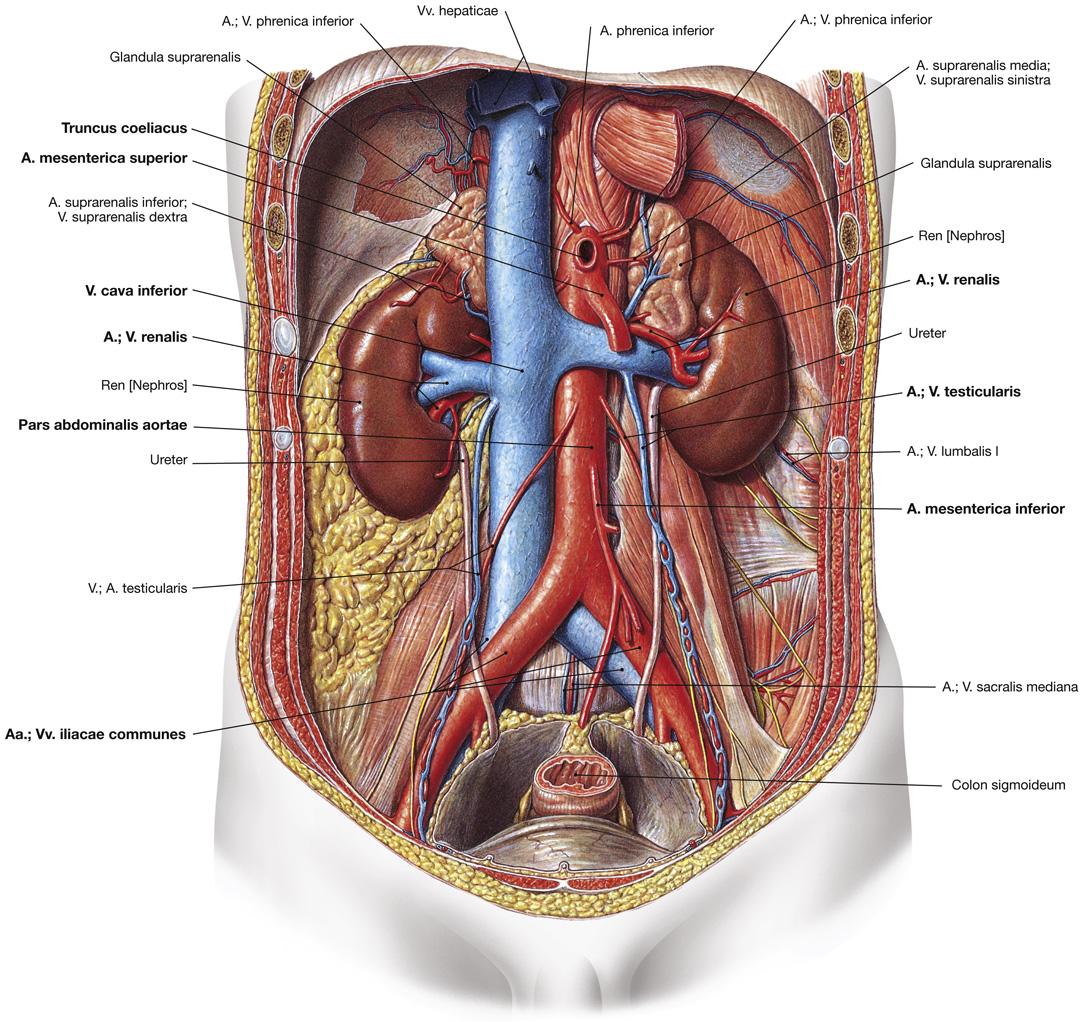

Fig 3.21: Aorta abdominalis

|